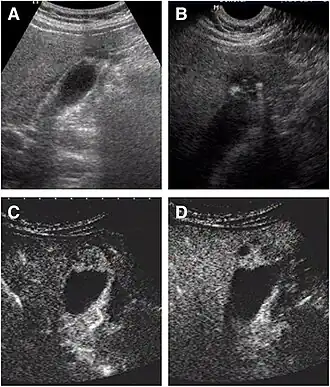

Non-contrast abdominal ultrasound and contrast-enhanced ultrasound (CEUS) of adenomyomatosis of the gallbladder:[3]

a The fundus of the gallbladder wall was thickened and the GB wall was obscure.

b The intramural echogenic foci were detected by high frequency transducer.

c CEUS—arterial phase (22 s) —heterogeneous hyper-enhancement and wall was intact.

d CEUS—venous phase (34 s) the anechoic spaces were more clear.